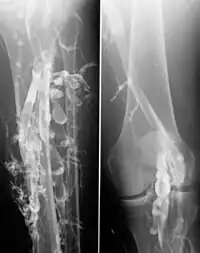

Flebografia de um paciente com trombose venosa profunda.

Era um exame usado para diagnosticar trombose venosa profunda, porém atualmente já não é usado para este fim pois a Ecografia e o doppler vieram facilitar o diagnóstico pela precisão, conforto para o doente e menor custo. Pode eventualmente ser usado para fins de investigação ou em certos casos de malformações venosas.[1]